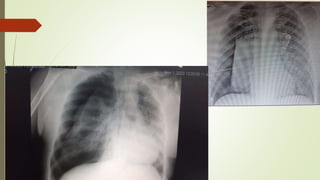

Exemplo:

4Q’s:

Está é uma radiografia de tórax em PA, da D. Ana,

feita no dia 10 de março de 2021. O Exame está bem

penetrado, não está rodado e há inspiração

adequada.

ABCDE:

A: a traqueia está centralizada.

B: os campos pulmonares estão expandidos

simetricamente e claros.

C: o tamanho do coração está normal. Os contornos

mediastinais e os hilos não apresentam alterações

ao método.

D: não há evidência de derrames ou hérnias.

E: não há evidencia de fratura, pneumoperitôneo,

enfisema ou corpos estranhos.